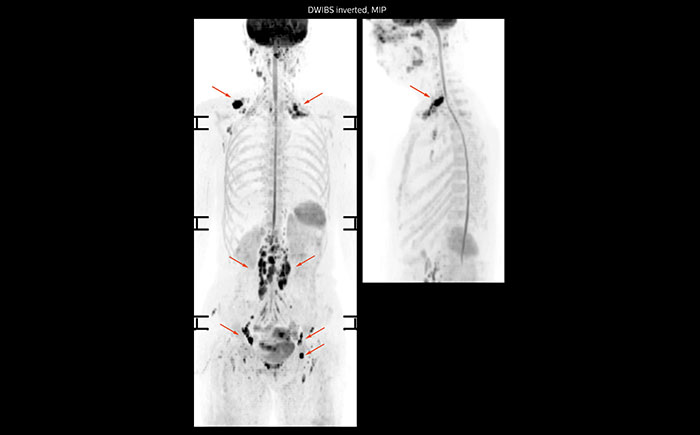

A 61-year-old female with a malignant lymphoma underwent an MRI exam with whole body diffusion weighted imaging (DWIBS) as well as PET. On the images shown, the resolution of DWIBS is better than PET, which allows visualization of the small pelvic lesions and almost no distortion is seen in the neck area.